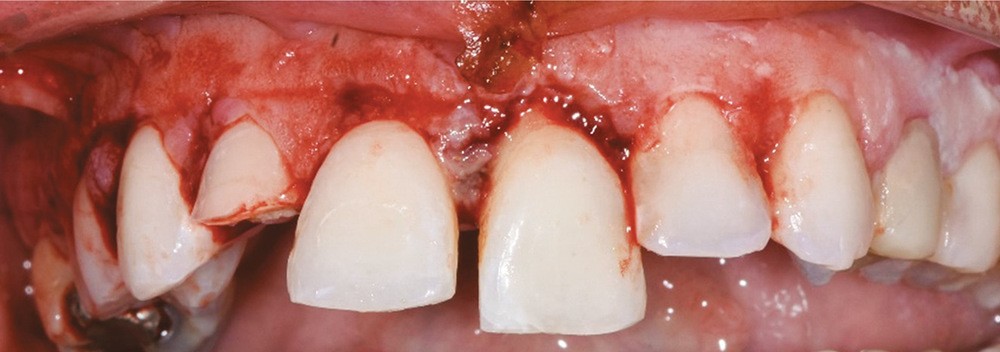

c. Dépose pour remplacer la contention par un dispositif flexible. (patiente du Dr Wagner traitée en collaboration avec le Dr Lutz, service de chirurgie maxillo-faciale et stomatologie, Hôpitaux Universitaires de Strasbourg)